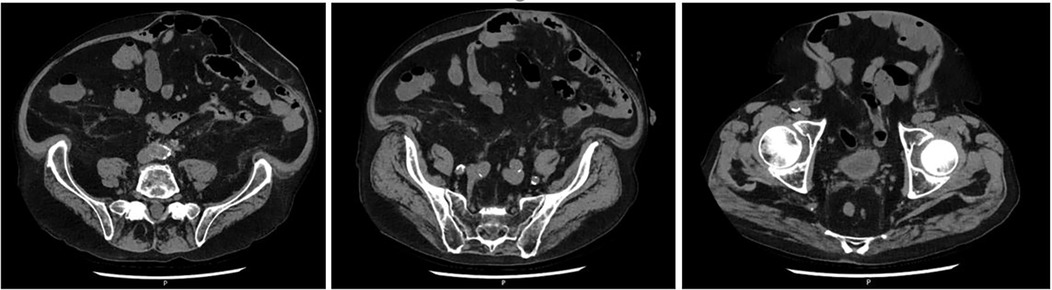

Figure 4

Ultrasound images of an incisional hernia (H) measuring 26 mm in width with the underlying surgical mesh (M) visualized. The hernia sac is seen protruding above the mesh plane.

Figure 4. Ultrasound images at 43 months follow-up of a 70-year-old patient who underwent re-laparotomy 18 months after AAA repair for an adenocarcinoma of the gastroesophageal junction. (A) 26 mm. supra-umbilical hernia. (B) Ultrasound image showing the retro-muscular mesh in place M, mesh; H, hernia.